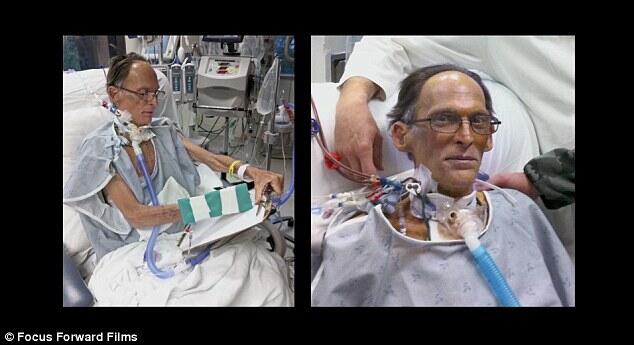

Pada bulan Maret tahun lalu, Craig Lewis, 55, dalam kondisi sekarat karena kondisi jantung yang menyebabkan pembentukan protein abnormal, dengan kondisi ini bahkan alat pacu jantung tak dapat membantu menyelamatkan hidupnya. Craig Lewis (55), adalah orang pertama yang menggunakan pompa 'aliran kontinu' untuk menggantikan fungsi jantung Tapi dua dokter dari Texas Heart Institute mengusulkan solusi baru yang revolusioner, yakni menginstal perangkat yang akan memungkinkan darah bersirkulasi dalam tubuhnya tanpa denyut jantung.

Dr Billy Cohn dan Dr Bud Frazier kemudian menginstal perangkat tersebut setelah mengeluarkan jantung Lewis. Dan dalam waktu beberapa hari, sang pasien sudah bangun dan berbicara dengan dokter.

Jadi, dengan izin isteri Lewis yaitu Linda, Dr Cohn dan Dr Frazier kemudia memasang alat ini pada Maret 2011.

Perangkat tersebut bekerja dengan memasok aliran darah secara kontinu melalui tubuh, dengan menggunakan baling-baling.

"Saya mendengarkan bunyi dengungan yang menakjubkan. Dia tidak punya denyut jantung." tutur isterinya yang keheranan.